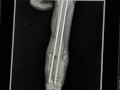

Wir haben voller Hoffnung gewartet mit der Publikation glaubten aber fast nicht daran! Beni wurde verunfallt in Bensergao Marokko gefunden mehr tot als lebendig. Die Vorderbeine waren ganz offensichtlich gebrochen und da sie die Hinterbeine nicht bewegte war das Rückgrat sicher auch beschädigt. Trotzdem zeigte sie ganz kleine Bewegungen und der Schwanz wedelte ebenfalls ganz leicht. Vorsichtig wurde sie geborgen und auf die Ferme gebracht. Dort zeigte sie ganz klar ihre Lebensfreude und den Willen, weiterleben zu wollen. Gestern wurde sie nun nach Marrakkesh gebracht und die Vorderbeine operiert. Drücken wir ihr ganz ganz fest die Daumen und Pfoten, dass auch ihr Rückgrat langsam wieder heilt und sie wieder laufen lernt. Helft ihr mit, die Kosten für sie zu tragen?